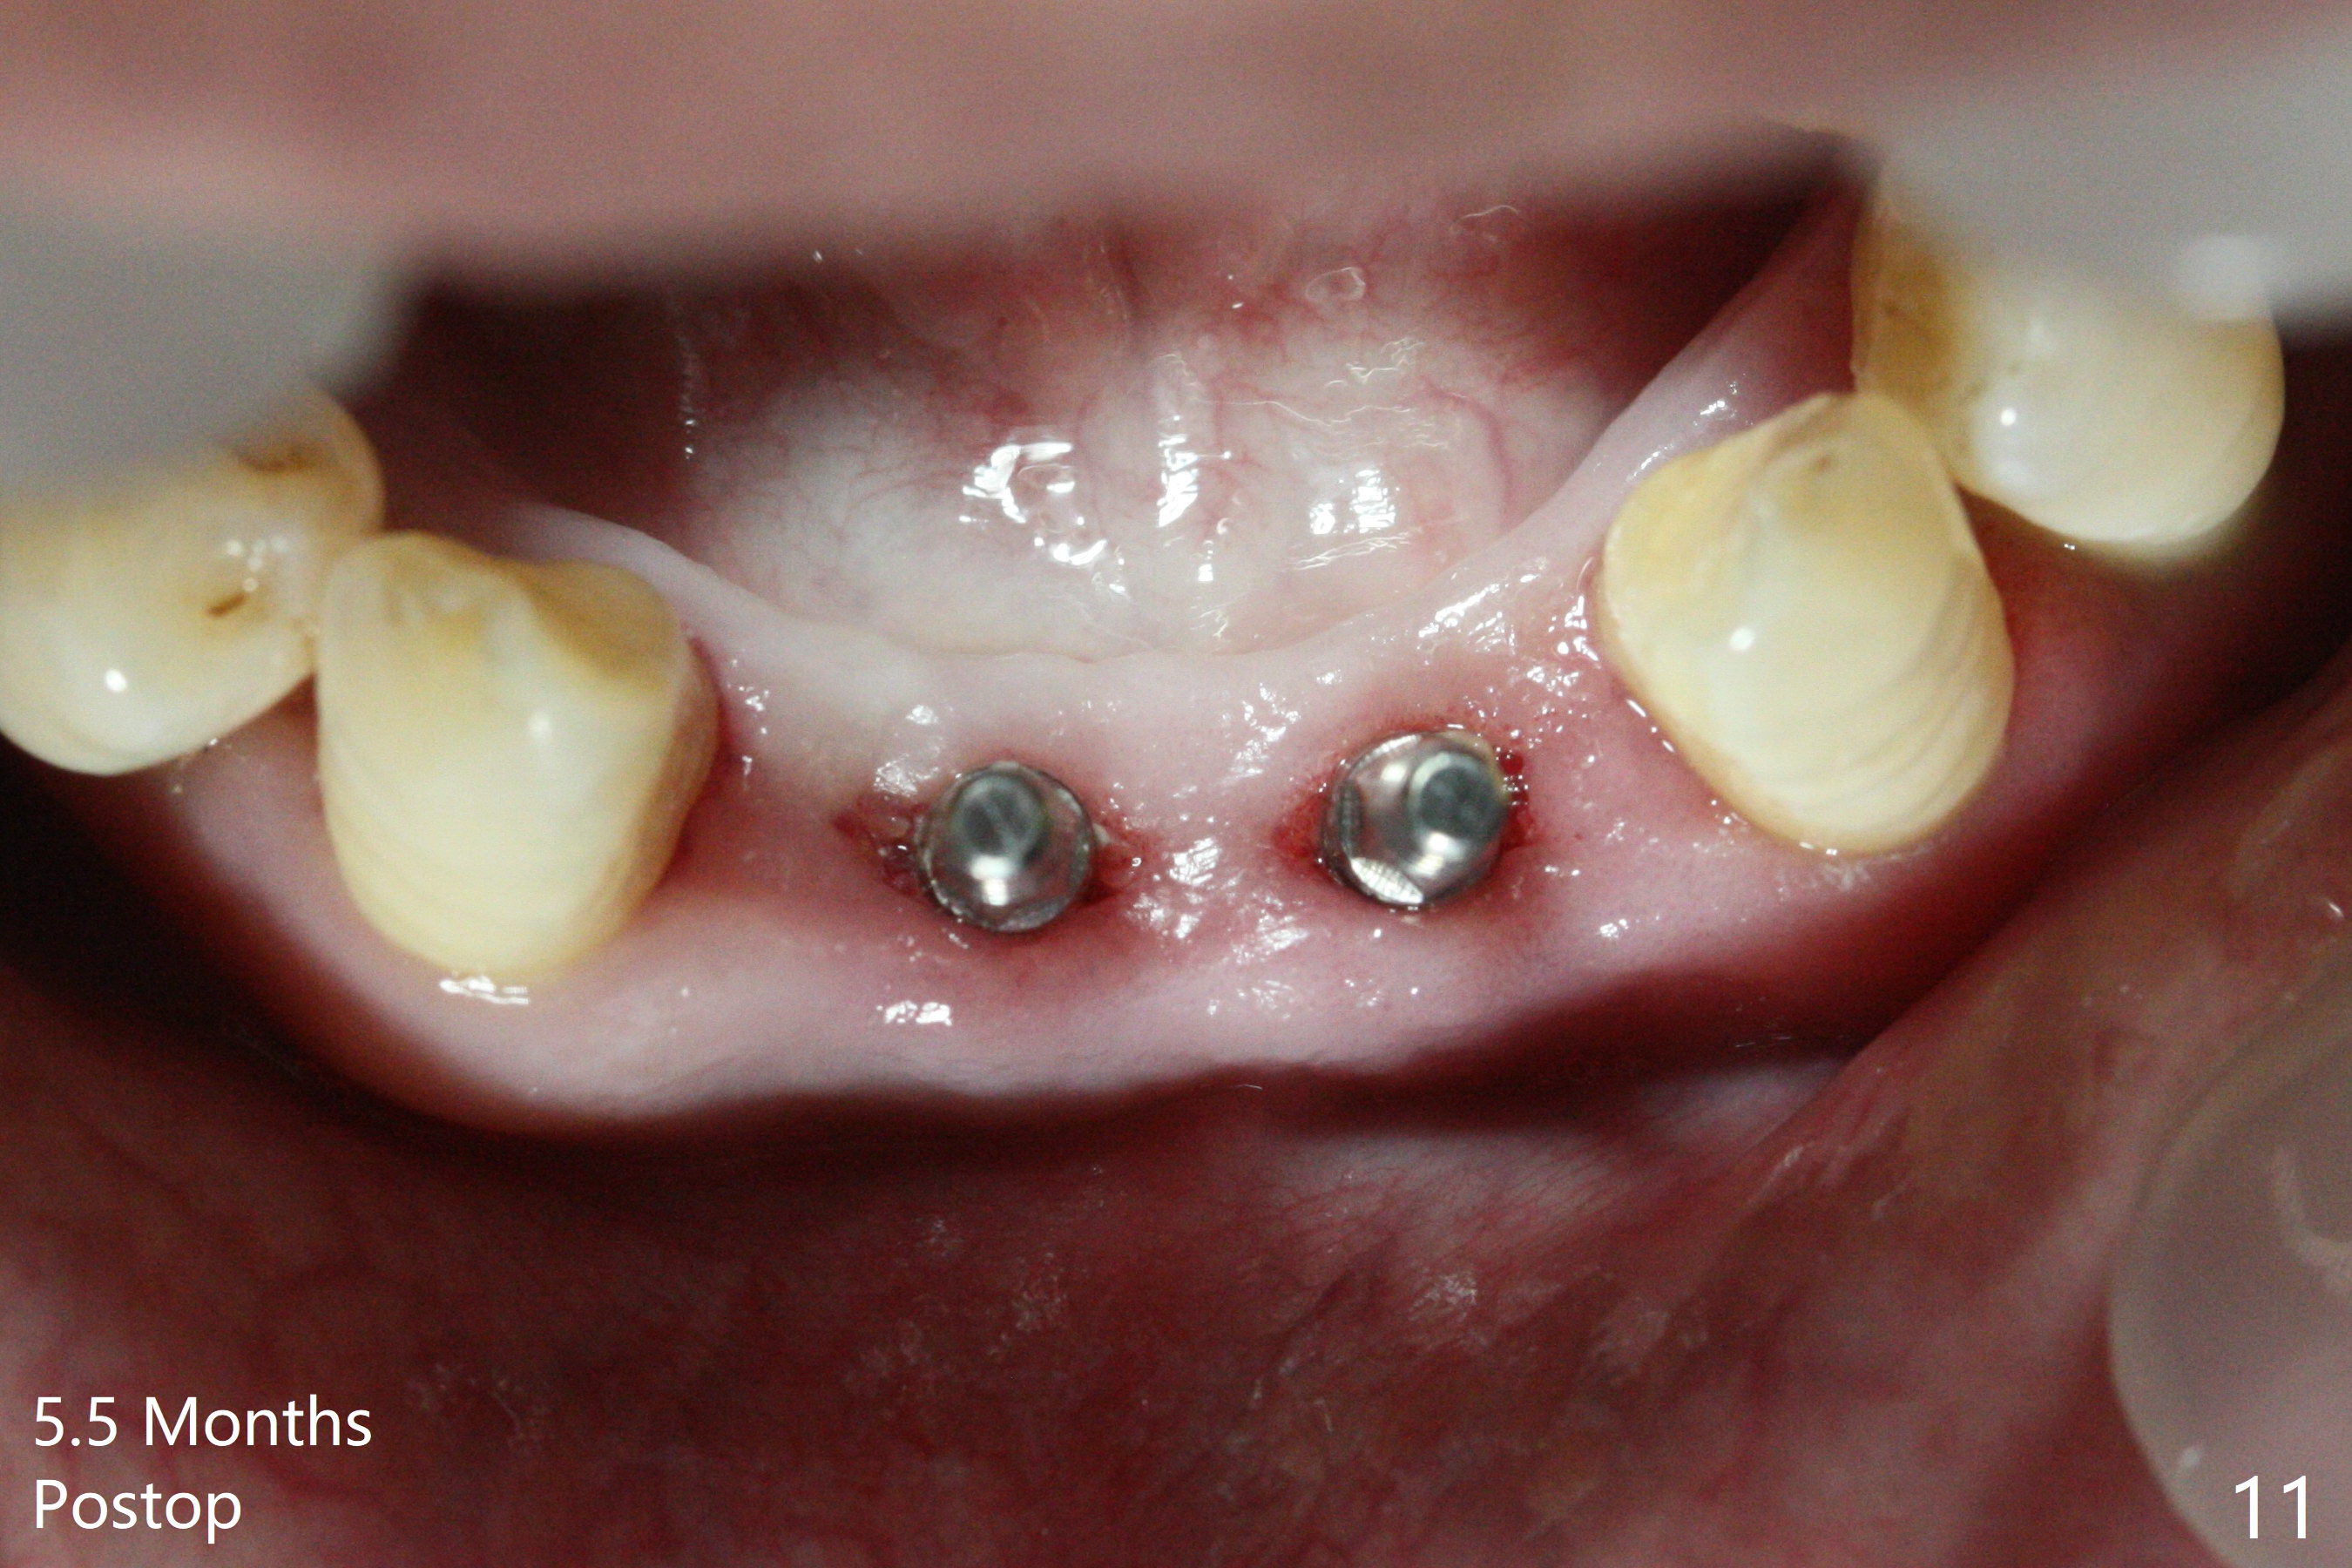

After extraction of 4 of the lower incisors, there are basically 2 sockets (#23/24 and 25/26), separated by the apparently midline bone (Fig.1 red line).  In spite of using Lindamann bur to move the 25/26 osteotomy mesially, a 3x14(2) mm dummy implant remains close to the tooth #27 (Fig.2).  The terminal branch of the Incisive Canal (<) is located between the lateral and central incisors.  A de novo osteotomy (Fig.3 (1.5 mm drill)) is made mesial to the original one (O).  While the 3x14(2) mm dummy implant is incompletely placed at #25/26, a 3x14(4) mm 1-piece one is placed at #23/24 (Fig.4).  Finally the same implant is placed at #25/26 with placement of mineralized cortical/cancellous bone (Fig.5 *).  When the large sockets are sutured, the supraerupted teeth #7-9 touch the lower gingiva (Fig.6).  The incisal edge is reduced for clearance (Fig.7).  Periodontal dressing is less likely to be dislodged with the incisal edge reduction (Fig.8,9).  A provisional FPD is fabricated 1 week postop.  Hard (Fig.10) and soft (Fig.11,12) tissues heal 5.5 months postop.  The patient returns for crown cementation 3 months post impression (9 months postop, Fig.13,14).